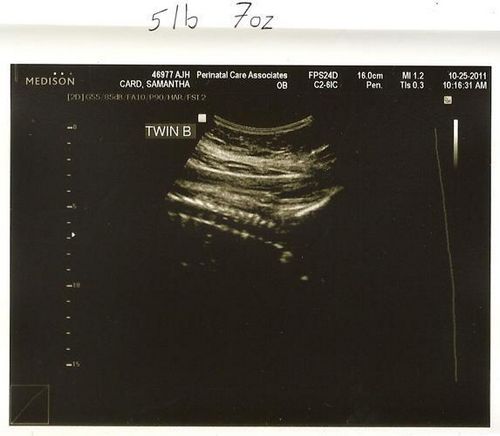

На 36 тижні вагітності фото дитини може бути зроблено в період, коли він не спить і мама зможе розгледіти, що його щоки округлилися і він значно виріс. Всі органи малюка повністю сформувалися, триває розвиток нервової системи і зміцнюються кістки. Обов'язково треба, щоб мама була морально готова до пологів, якщо вагітність багатоплідна або пізня. Тому що в цьому випадку 36 тиждень вагітності, фото якої зроблять в медичному центрі при обстеженні, може стати першим тижнем життя малюка або малюків.